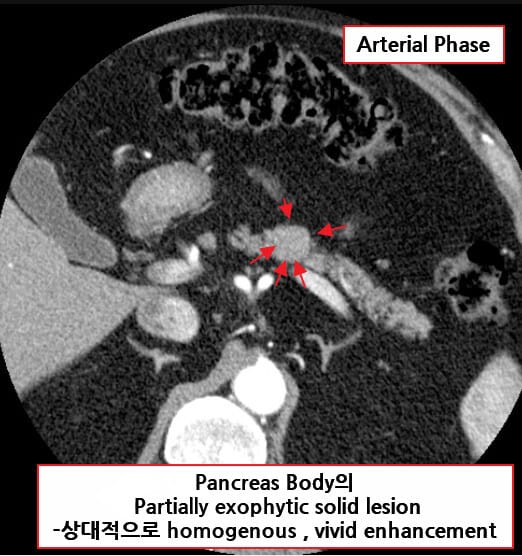

영상소견

췌장의 종양 병변을 국소화하기 위해 다양한 영상검사를 시행합니다.

| 영상검사 소견 |

| 🔵 췌장 조영 CT 또는 MRI |

| 조영증강기(arterial phase)에서 조영이 잘 되는 작은 종양(1~2cm)을 확인할 수 있습니다. |